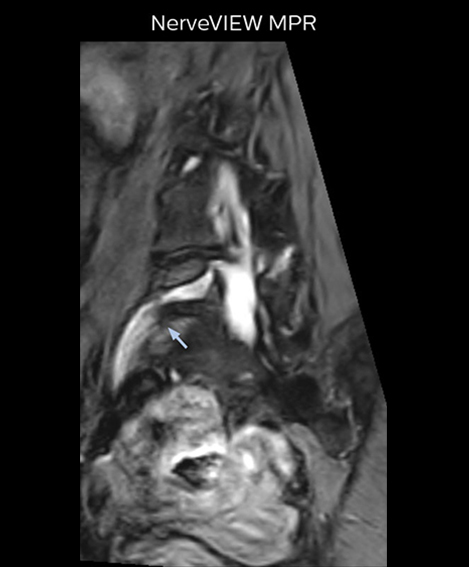

At Northern Fukushima Medical Center in Japan, excellent MRI visualization of nerves helps support confident diagnoses and informs surgical treatment decisions for patients with lower limb symptoms. MRI technologist Tanji and orthopedic surgeon Dr. Yabuki share how direct nerve visualization with the 3D NerveVIEW method adds information when diagnosing atypical herniations. The additional insights changed their way of working and benefit their patient care, as illustrated by some clinical examples.

“In patients with lower extremity neurological symptoms, NerveVIEW helps us to determine the disease matching the patient’s symptoms by directly visualizing the nerves. We use the sequence mainly, when there is suspicion of intraforaminal stenosis, extraforaminal stenosis or lateral disc herniation, which is often based on routine T2- and T1-weighted images. Additionally, the excellent depiction of the course of nerves makes NerveVIEW a good navigator when applying treatment such as block therapy or surgery.”

“For example, in sagittal images, when the presence of fat is observed in the intervertebral foramen, it suggests that there is a margin around the nerve. Similarly, the absence of fat indicates that the nerve is being compressed. So, we used to deduce nerve compression indirectly. With NerveVIEW, however, we can observe the condition of the nerves directly, regardless of the presence or absence of fat. We always prefer such direct observation of anatomy over having to make an inference about it.”

“Although symptoms of typical disc herniation and atypical hernia are very similar, the actual site of herniation is different. It is therefore important to characterize the nerve’s condition both inside and outside of the intervertebral foramina. “Conversely, if we see no abnormality in NerveVIEW, we can assume at least that there is no severe condition that requires surgery. Like this, it can help us avoid unnecessary surgery. NerveVIEW can have a tremendous impact in this way.”

“NerveVIEW is really useful for those cases where a nerve disorder is strongly suspected based on the clinical examination but our regular MRI images do not show any findings. These atypical herniations and spinal canal stenosis, occurring in 5% to 15% of the total lumbar herniation/stenosis cases are our main target when using NerveVIEW,” says Dr. Yabuki.

“The intra-luminal signal of veins, especially around the intervertebral space, can be suppressed well with NerveVIEW. As a result, we can easily observe the detailed nerve structure around the posterior ganglion,” he says. “This is why we use 3D NerveVIEW for intraforaminal stenosis and extraforaminal stenosis/herniation (lateral disc herniation). On the other hand, if herniation is suspected to exist inside the dorsal root ganglion (DRG), balanced TFE or ProSet-FFE is applied. NerveVIEW is not suitable for evaluating the median type of herniation.” The SE-EPI DWI-based method for MR neurography works well for large FOV exams like whole-body MRI, but focal examination of nerves is often limited by the attainable spatial resolution (both inplane and slice direction) and geometric distortion. “3D NerveVIEW achieves higher in-plane resolution – close to our other routine spine sequences – and the source images can be used instead of adding a fat-suppressed T2-weighted sequence,” Tanji says.